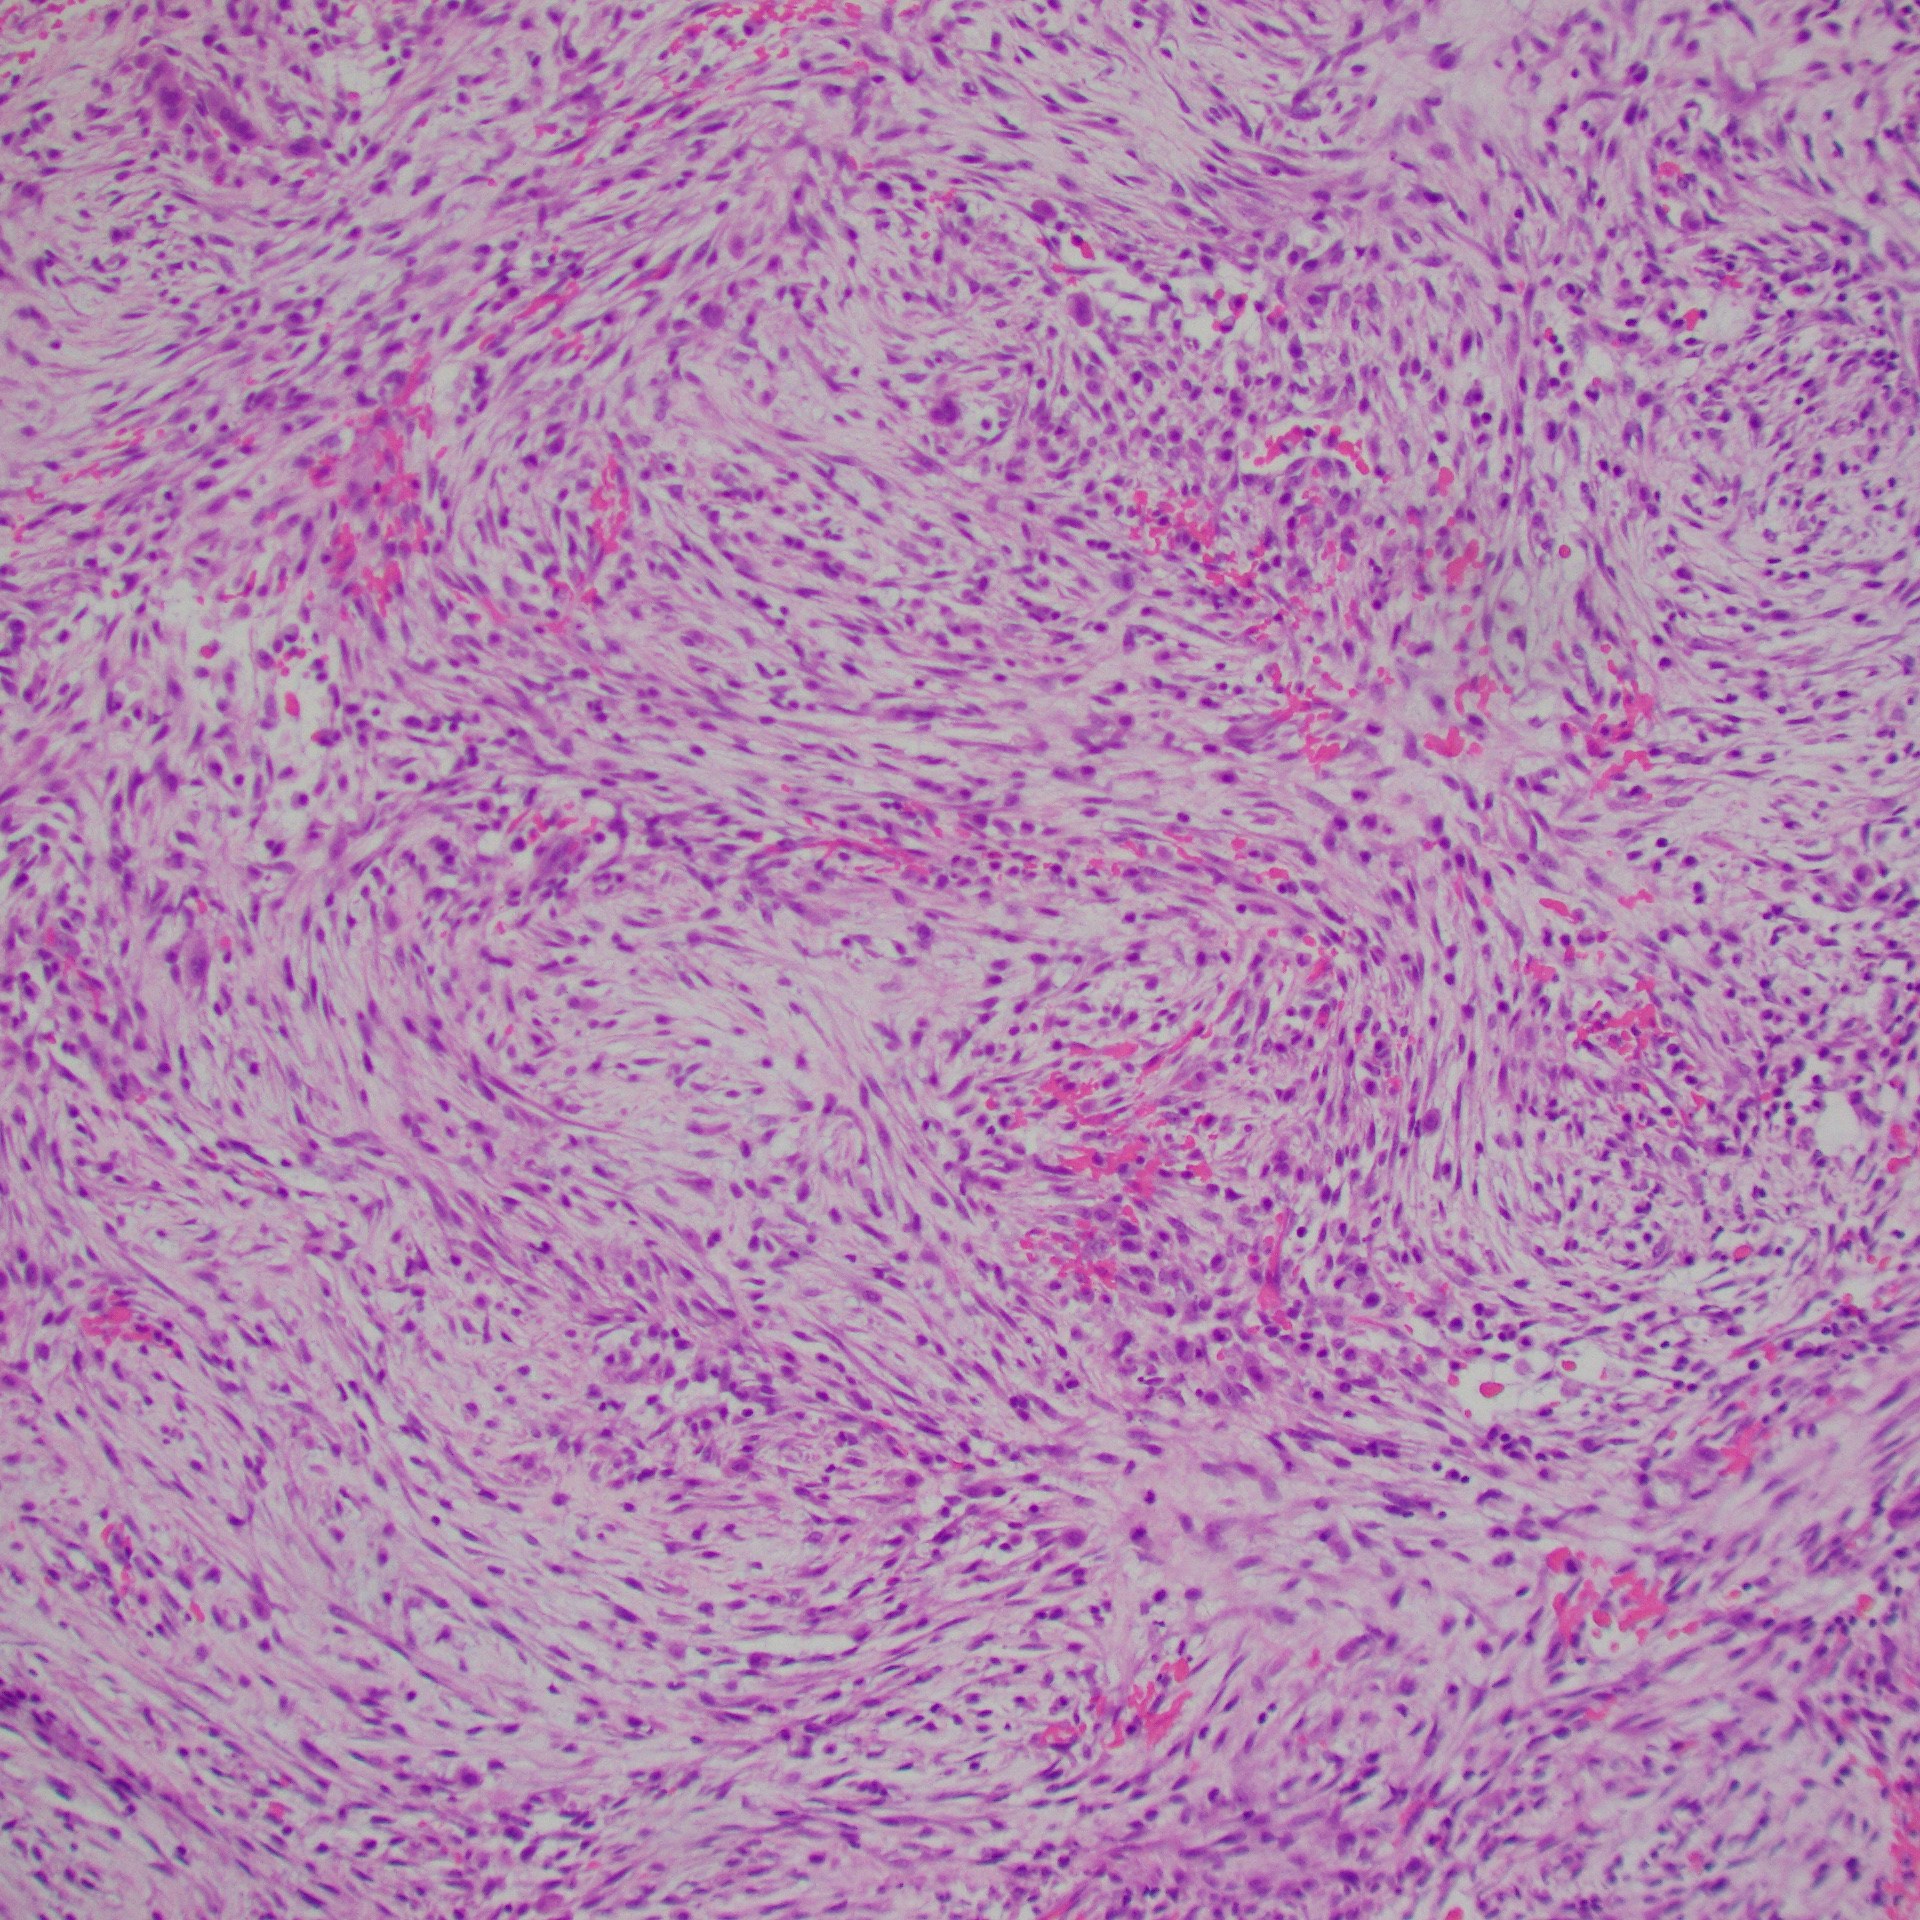

Nodular Fasciitis

- Fibroblastic spindle cell proliferation

- Tissue culture-like growth pattern, bland nuclei

- Mitotic activity can be frequent (but not atypical)

- Variable cellularity

- Extracellular matrix ranges from myxoid to collagenous (older lesions may be more collagenous)

- Scattered lymphocytes, histiocytes, and osteoclast-type giant cells often present

- Areas of cystic degeneration may be identified

- Majority: MYH9::USP6 fusion; other fusion partners possible